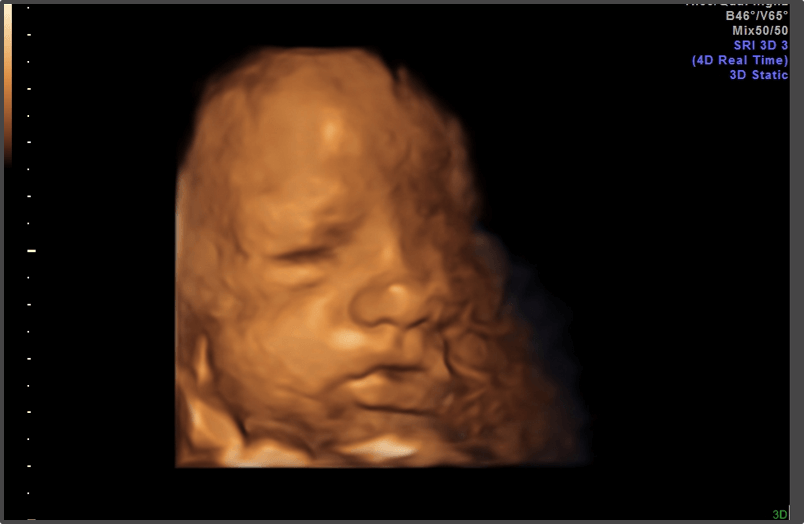

Your baby is the size of a watermelon.

Baby is the size of Mini Watermelon

Approx Baby Weight: 3.3kg

Approx Baby Size: 50.7 cm

The baby is now fully developed and ready for delivery.